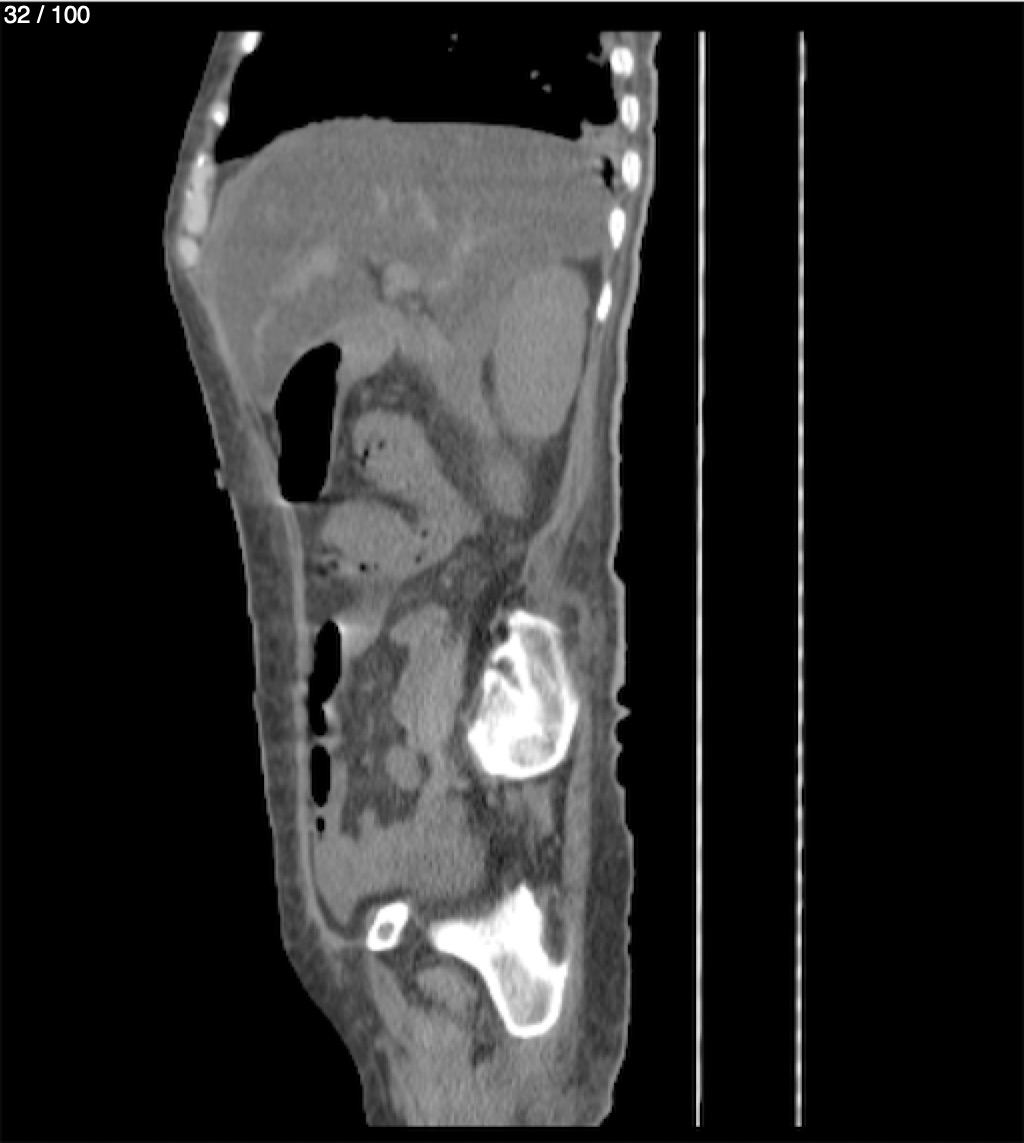

Hilda Geronimo Mendez 60A - T.C Abdomen Simple